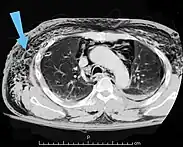

Bubbles of air in the subcutaneous tissue (arrow) feel like mobile nodules that move around easily